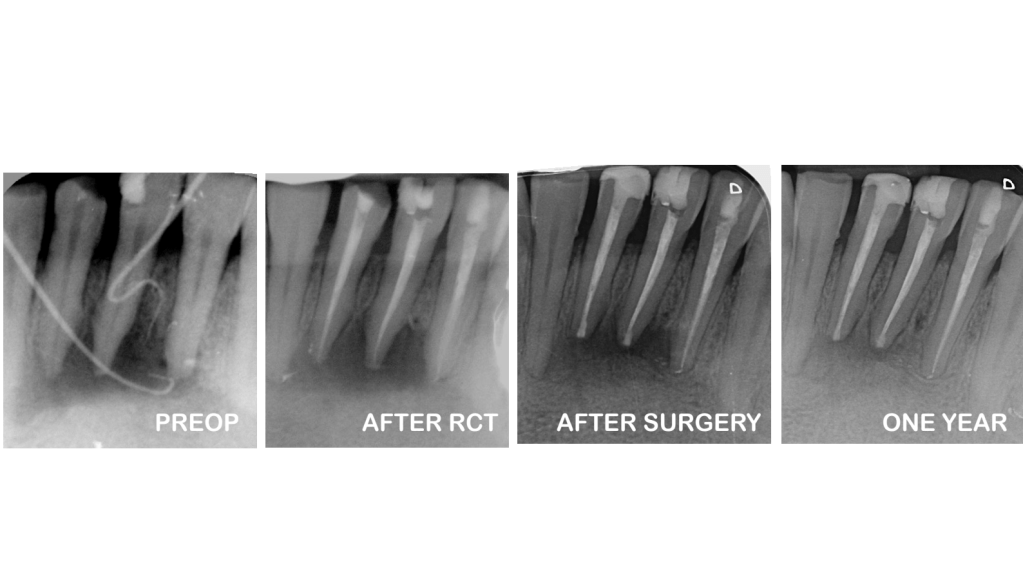

Cirugía apical